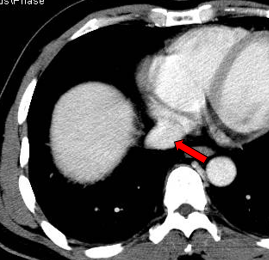

现病史:2011年01月4日于当地医院行PET/CT: 1. 肝左外叶肝癌并肝门区淋巴结转移,2. 下腔静脉及右心房结癌栓,考虑为”原发性肝癌“。

肝左叶巨块型肝癌(13.8cm×9.1cm),伴肝右后叶子灶,门静脉左支、肝左静脉及下腔静脉内癌栓。